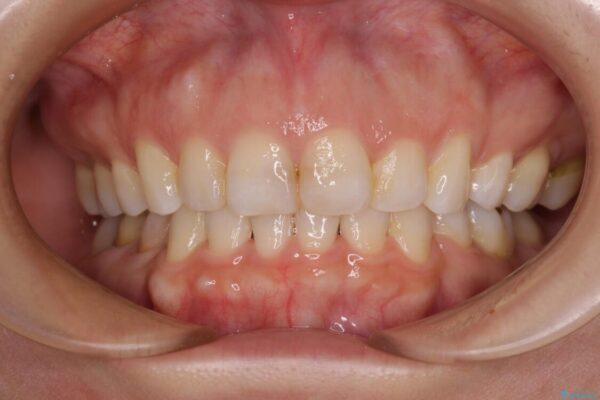

治療後

• 【モニター】出っ歯と咬み合わせを改善 ワイヤー装置の抜歯矯正 治療後画像

治療後について

奥歯の咬み合わせ改善には1年ほどの期間と処置中の噛みにくさを強いることとなりましたが、抜歯後はスムーズに治療を完了させることができました。

歯ぎしりの際に奥歯が干渉していた咬み合わせも理想的な状態に改善できました。